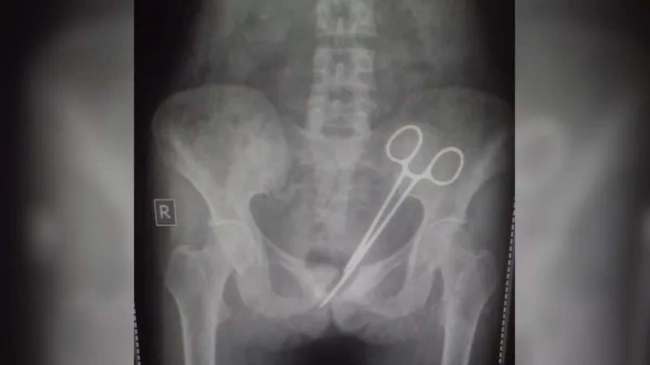

Doctors Leave Pair Of Scissors In Woman Abdomen: इलाज में लापरवाही का बड़ा मामला सामने आया है। दरअसल, एक महिला के ऑपरेशन के 12 साल बाद पता चला कि डॉक्टरों ने उसके पेट में सर्जिकल कैंची छोड़ दी। फिलहाल महिला के पेट से कैंची निकाल ली गई है। वह अभी अस्पताल में भर्ती है और उसकी हालत स्थिर बनी हुई है।

मीडिया रिपोर्ट्स के अनुसार ऑपरेशन के कुछ दिन बाद महिला के पेट में फिर दर्द होने लगा। उसने दर्द के लिए कई डॉक्टरों से दवा ली लेकिन उसे आराम नहीं आया। इसके बाद 8 अक्टूबर 2024 को वह फिर एसटीएनएम अस्पताल पहुंची। यहां डॉक्टरों ने उसका एक्सरे किया तो वह हैरान रह गए, उसके पेट में सर्जिकल कैंची थी। आनन-फानन में उसे एडमिट किया गया। जांच के बाद उसका ऑपरेशन कर कैंची पेट से बाहर निकाली गई।